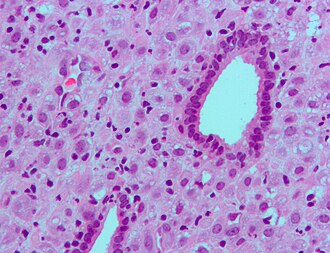

Endometrium with hormonal changes due to the OCP. H&E stain. | |

| LM | inactive glands (round/ovoid glands, simple cuboidal epithelium, no mitoses), decidualized stroma (nucleus central, eosinophilic cytoplasm, well-defined cell borders) |

- Inactive glands (round/ovoid glands, simple cuboidal epithelium, no mitoses).

- Stroma decidualized -- mnemonic NEW:

- Nucleus central.

- Eosinophilic cytoplasm.

- Well-defined cell borders.